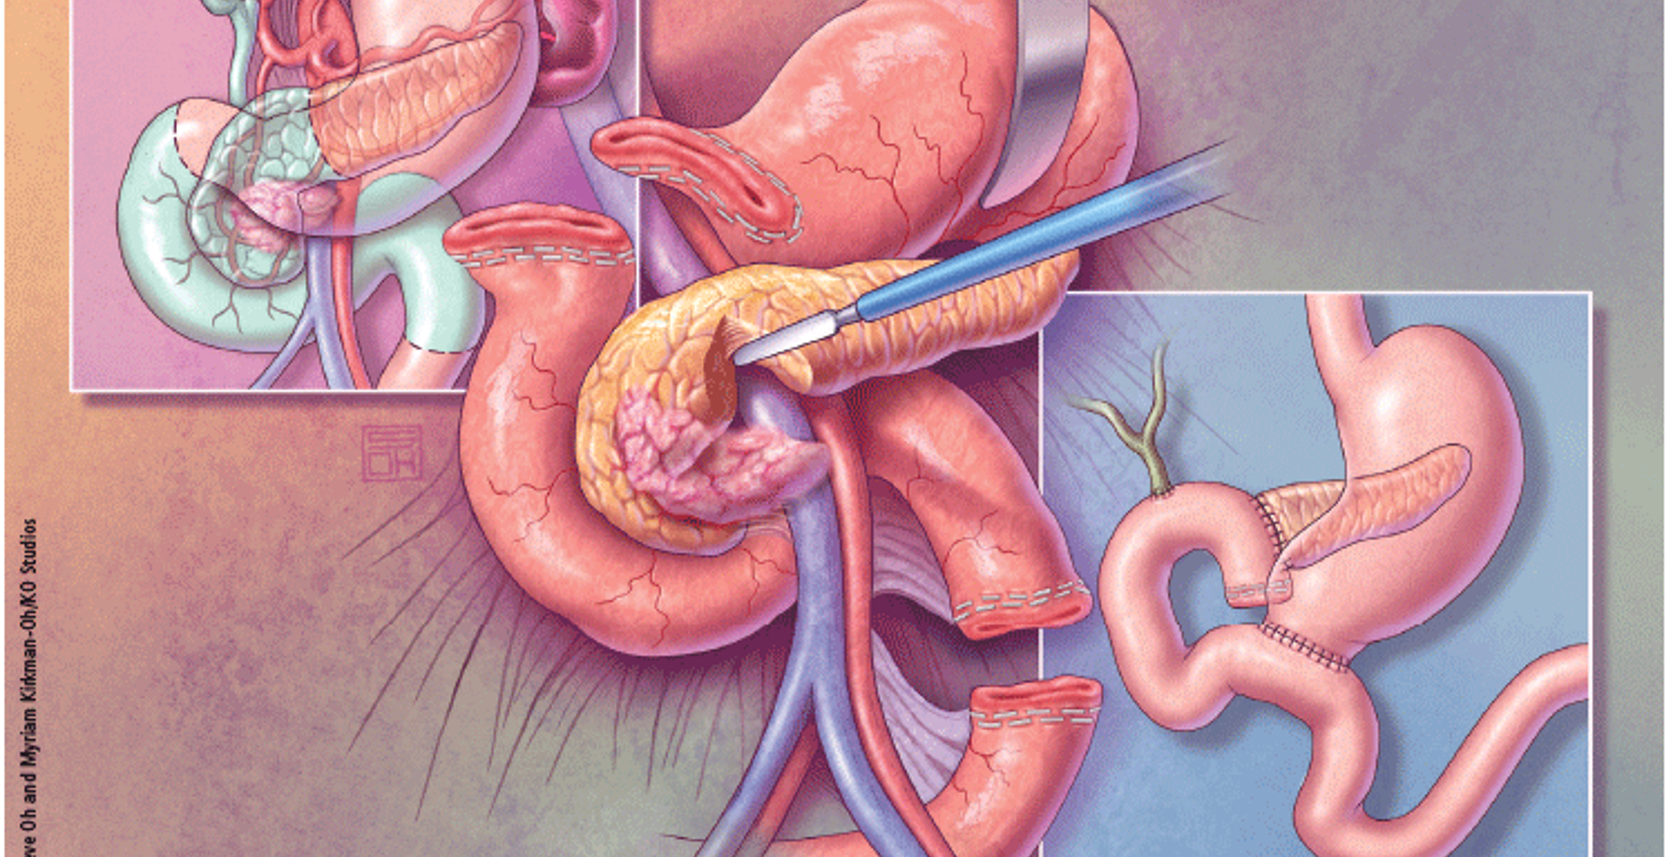

Tumors involving the head of the pancreas are treated by pancreaticoduodenectomy (Whipple’s procedure), which entails block resection of the head of the pancreas, the distal half of the stomach, the duodenum, gallbladder, and common bile duct.

Whipple’s procedure

Distal pancreatectomy